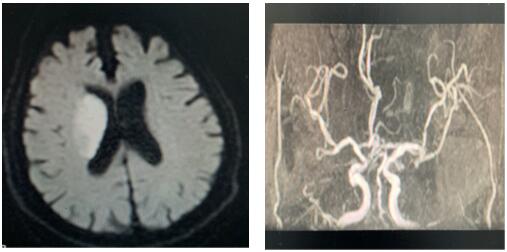

患者治療前影像圖

戰(zhàn)疫情,防卒中,我們刻不容緩!2020年2月14日,同往常一樣,卒中中心接診一名65歲患者,突發(fā)右側(cè)肢體活動(dòng)不靈,卒中急診張帆醫(yī)師迅速判斷,考慮急性缺血性腦卒中,在NICU王偉偉副主任帶領(lǐng)下反復(fù)排查新型冠狀病毒感染,溶栓治療工作有條不紊,張沖醫(yī)師嚴(yán)密觀察患者生命體征,溶栓效果及不良反應(yīng),治療后右側(cè)肢體肌力恢復(fù)4級(jí),基本生活自理,達(dá)到溶栓效果。這是我們工作的常態(tài)!無(wú)論疫情是否,我們卒中人始終堅(jiān)守一線,從進(jìn)入NICU,一直到他們帶著笑容走出大門,那一張張笑臉是我們繼續(xù)堅(jiān)持的動(dòng)力!